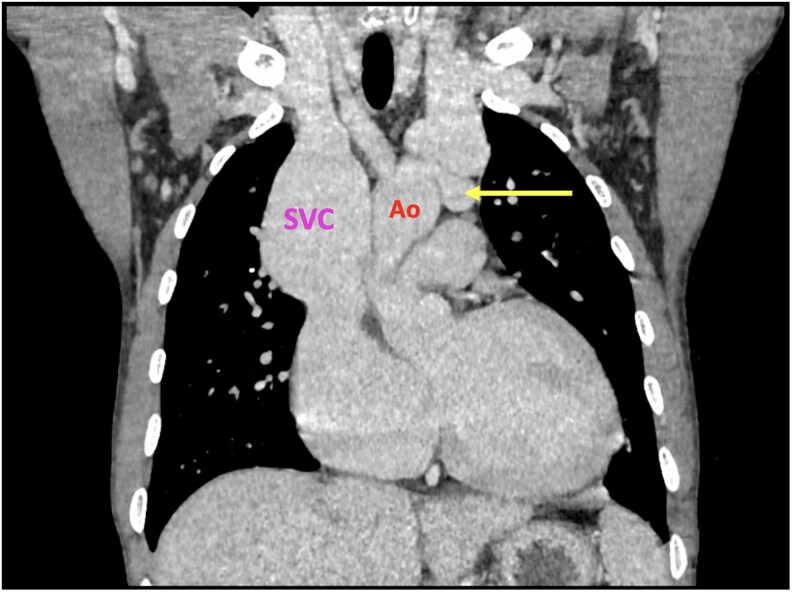

Case summary: We present the case of a 38-year-old male patient with a history trauma from a localized bombing, resulting in shrapnel impact to his thorax. He came for surgical treatment due to a diagnosis of arteriovenous fistula at the level of the aortic arch. For surgical planning, two 3D models (with FDM and PolyJet technology) were made to assess the anatomical relationship between the aorta, the left brachiocephalic vein, the fistulous tract and the sternum. The patient was successfully operated on.

Discussion: Surgical repair of thoracic fistulas is highly complex, requiring a multi-disciplinary approach and advanced imaging for accurate diagnosis and planning. Procedures are often performed under cardiopulmonary bypass and hypothermia to enhance safety, especially in challenging scenarios. These fistulas frequently cause vascular overload and degenerative venous changes, increasing the risk of haemorrhage and complicating dissection. 3D technology significantly improves surgical planning by enabling accurate fistula localization, guiding sternotomy, simulating procedures, and mapping vascular anomalies. PolyJet models, in particular, provide superior anatomical insight. Thus, 3D modelling serves as a complementary tool that provides life-size, detailed anatomical information of the patient, facilitating better pre-operative surgical planning, and carrying the potential to reduce operative risks.